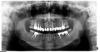

Doc Опубликовано 27 июля, 2011 Поделиться Опубликовано 27 июля, 2011 Док, я не уловил... снимки сделаны 11 лет назад? Т.е. тогда, когда делалась вся работа? Тогда что они доказывают? Не понимаю...По возникшему спору... Если даже не брать 11 лет назад, 20 лет назад... Какой на сегодня статистический успех эндо? Есть такие данные? Причем даже не столько первичного, сколько повторного. Что за люди. Даже мне не верят. Что творится на белом свете?!Одна орто 11 лет, вторая шесть лет, написал же. Раз мало, то прилагаю орто этой же пациентки, правда позапрошлый год, с тех пор на контроль не приходила, извините уж. Письменные доказательства с собственноручной подписью пациентки и карточку из той клиники, где все это делалось требовать будете? А то сложно будет достать, ее подпись огромных денег стоит, а карточку в той клинике мне не отдадут. Ссылка на комментарий

Doc Опубликовано 27 июля, 2011 Поделиться Опубликовано 27 июля, 2011 Да я про первый снимок спрашивал... в котором 8-ки и эндо вопросы вызвало... Эмиль Гургеныч, не вставайте в оборонительную позу, я не нападаю. Я просто не уловил что это за снимок, в котором работе 11 лет. Ситуация сразу после протезирования или это контрольный снимок через 11 лет, т.е. вот прямо свежий? Вот самый свежий. 12 11 2007 год. К сожалению свежее нет, пациентка не является на контрольные осмотры, видимо все у нее хорошо. Но в 2007 году этой работе было уже семь лет, они вместе с той делались. Первый снимок не могу датировать, т.к. он сосканированный с пленки в тиффе и там нет даты. Второй снимок уже с ортопантомографа, потому дата зашита в названии файла. Сейчас попрошу админов, чтобы позвонили и еще раз пригласили, сделаем более качественное орто. Если придет, то вывешу. Вы мне вроде вопросов не задавали. А мой вопрос был не к Вам лично, а ко всем. Ну так такой же вопрос уже дважды задавали, я же тоже не могу отвечать каждому отдельно одно и то же, потому тоже отвечаю всем. Ссылка на комментарий

Doc Опубликовано 28 июля, 2011 Поделиться Опубликовано 28 июля, 2011 Отказались от разборных в пользу не разборных. золото рулит, чаще к сожелению приходится ставить не драг. сплав., там чаще корни трещат. Но я думаю трещины корня не всегда собственно от наличия или отсутствия вкладки, проблемы раньше возникают на этапе ретрита... Ну так и зря отказались. Лучше было бы отточить мастерство на разборных, чем отказываться от них. Керамика тоже колется, Вы же не отказались от металлокерамики в пользу железа, а стали, наверное, изучать причины сколов, работать с прикусом и т.д. Если у Вас корни трещат от вкладок, значит просто "Вы их не умеете готовить". А если не трещат, а Вы отказались только потому, что кто-то где-то рассказал, что трещать, то не нужно опираться на слухи. Вот, как раз еще одна пациентка из того же далекого 2000 года. А вот эта же самая пациентка сегодня: Даже несмотря на то же самое "хреновое эндо", которое тот же самый врач делал, что и предыдущие случаи, живет и здравствует. Ни один зуб не требует вмешательства. Ссылка на комментарий